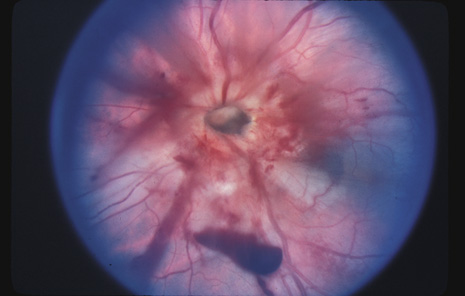

Another severe complication of blunt trauma is evulsion of the optic nerve (Fig. 26). Although this usually is accompanied by severe damage to other ocular tissues, it can be the sole manifestation of apparently minor direct trauma or even a blow to the occiput.

Fig. 26. An evulsed optic nerve and small vitreous hemorrhage.